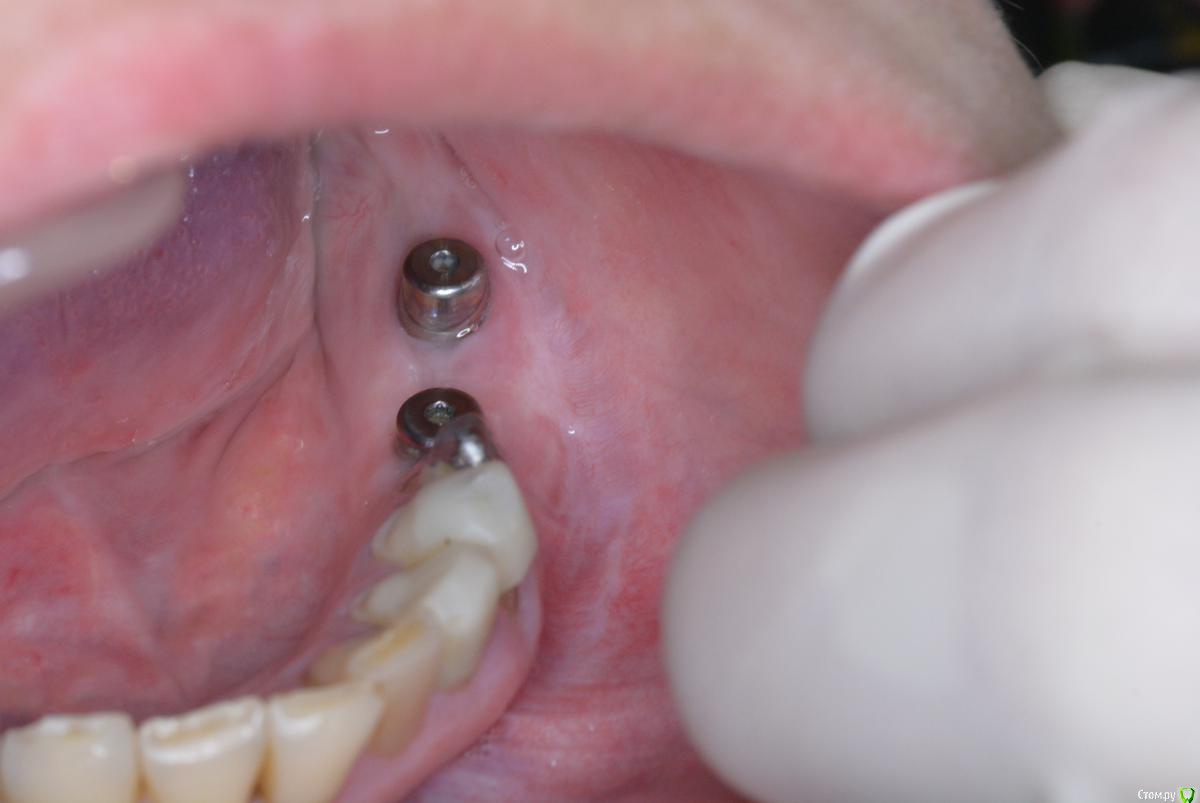

doktorenok Опубликовано 21 апреля, 2015 Поделиться Опубликовано 21 апреля, 2015 Ситуация следующая: в декабре 2013г проведена имплантация в 3 сегменте одномоментно с вертикальной аугментацией с применением мембраны Цитопласт (изначально над каналом было 4-5 мм). В июне 2014г раскрытие имплантов без манипуляций с мягкими тканями, ортопед вернул работу хирургу с просьбой сделать ткани прикрепленными. В июле 2014 г проведена пластика мягких тканей с применением Мукографта, направлен к ортопеду. Ортопед вернул хирургу с жалобами, что все подвижно. В ноябре 2014 г проведена операция углубления предверия по Казаньяну. На сегодняшний день ортопед опять недоволен, привел пациента ко мне и просит поправить ситуацию. Ситуация следующая: кератинизированной нет вообще, вестибулярно ткани очень тонкие, но прикрепленные, посередине между имплантов при натяжении щеки -слизистый тяж почти до середины гребня, язычно - ни прикрепленной, ни кератинизированной . Как бы Вы поступили? Варианты, которые вижу я:1. Оставить как есть, Пациент измучен. Но думаю будет периимплантит в ближайшем будущем.2. Вестибулярно- пересадка СДТ, язычно- деэпителизированный СДТ под расщепленный лоскут..3. Вестибулярно ничего не трогать, а язычно-деэпителизированный СДТ под расщепленный лоскут.4. Взять пошире СДТ , деэпителизировать его , надеть на формирователи и под расщепленный лоскут и язычно и вестибулярно.5. Заглушить импланты, пересадить СДТ. После приживления часть отдать на язычную сторону, а вестибулярную часть сместить апикально, или еще подсадить. Сама склоняюсь к 3 варианту.Проблема в том, что расщепить ткани вестибулярно будет сложно, они очень тонкие , будут рваться и разлезаться, и вестибулярно все очень бледное и в рубцах, то есть с кровоснабжением там плохо после нескольких хирургических вмешательств., боюсь получить некроз СДТ.Язычно - будет ли какой то результат от подсаженного деэпит. СДТ , учитывая тот факт, что кератинизированной нет вообще.На фотографиях все выглядит почему-то лучше, чем есть на самом деле. Фотограф я начинающий Поделитесь пожалуйста, кто как поступает в подобной ситуации? Ссылка на комментарий